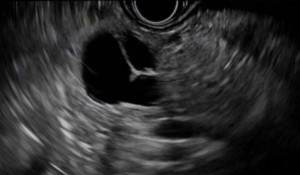

Mucinous cysts

Although most of them are benignant, there are risks of becoming malignant. Small size mucinous cysts are mostly discovered by chance, while large size mucinous cysts will cause abdominal pain. The most common type of mucinous cysts are:

- Intraductal papillary mucinous neoplasm (IPMN), with subtype main duct, branch duct and mix type.

- Mucinous cystic neoplasm (MCN)